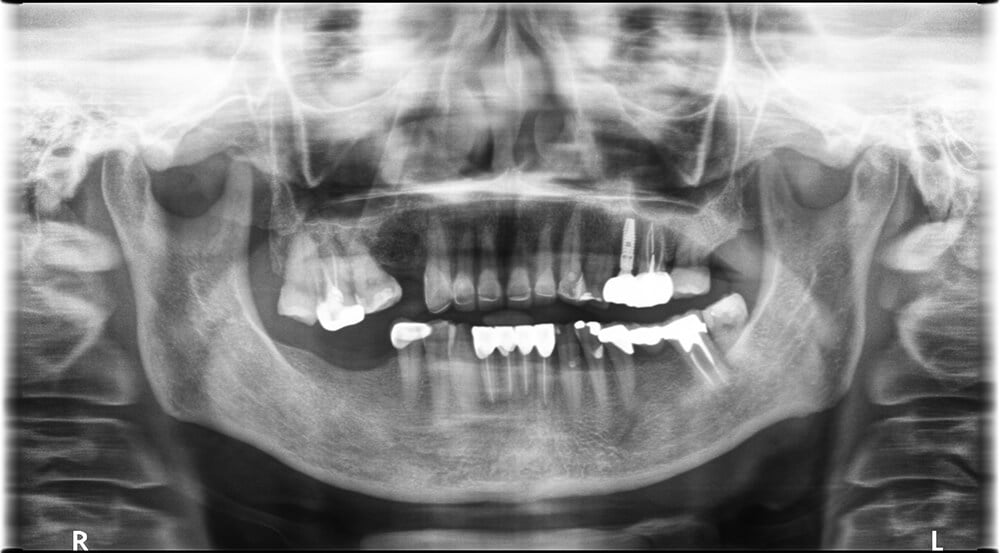

一般傳統植牙評估工具僅限全口X光片、電腦斷層及醫師經驗,醫師無法在手術前確認最終植體(人工牙根)植入位置。手術過程中,醫師必須經過一系列手術,切開牙齦皮瓣及翻瓣,露出齒槽骨後,依據手感及經驗來植入人工牙根,手術完再以縫線縫合。

• 牙科錐狀射束電腦斷層掃描(CBCT):術前準確模擬植牙角度及位置,安全性高,透過3D立體透視角度,傷口小、流血少、疼痛少、腫脹更少,牙科錐狀束電腦斷層劑量輻射量低,清晰3D影像有助醫師植牙時的角度定位,能縮短手術進行時間。